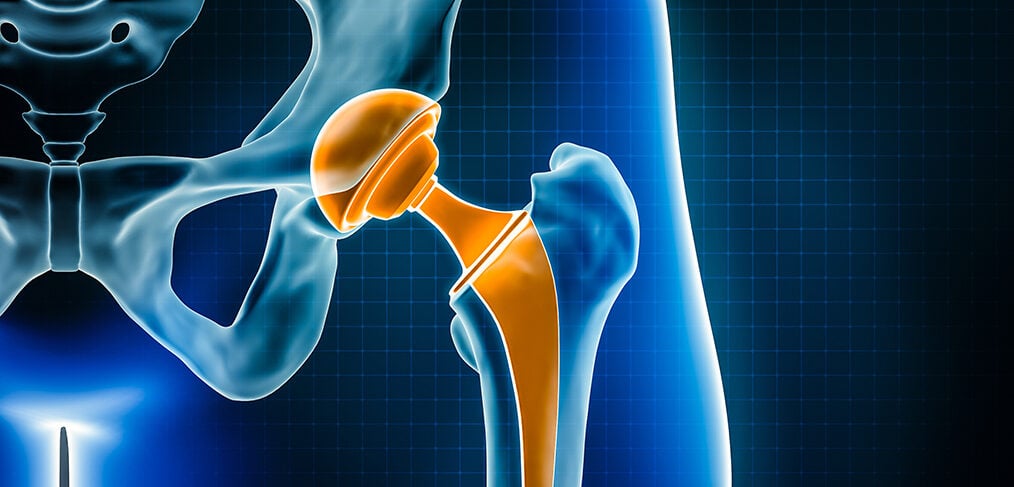

Total hip replacement surgery involves the use of various materials to create prosthetic components that replace the damaged parts of the hip joint. These materials are carefully selected for their durability, biocompatibility, and ability to replicate the natural movement of the hip. The primary components of a total hip replacement include the femoral stem, femoral head, acetabular cup, and a liner that fits within the acetabular cup.

The femoral stem, which is implanted into the thigh bone (femur), is typically made of metal alloys such as titanium or cobalt-chromium. Titanium is favored for its lightweight nature, strength, and excellent biocompatibility, allowing it to integrate well with the surrounding bone. Cobalt-chromium alloys are known for their high wear resistance and strength, making them suitable for the demanding environment of the hip joint.

The femoral head, which replaces the ball of the thigh bone, can be made of either metal or ceramic. Ceramic femoral heads are becoming increasingly popular due to their smooth surface, which reduces friction and wear against the acetabular cup. Metal femoral heads, often made of cobalt-chromium, are also commonly used for their durability and wear resistance.

The acetabular cup, which replaces the hip socket, is usually made of metal alloys such as titanium or cobalt-chromium. To reduce wear and provide a smooth articulation surface, the acetabular cup is often lined with a polyethylene (plastic) liner or a ceramic liner. Highly cross-linked polyethylene liners have improved wear resistance compared to traditional polyethylene, making them a popular choice for hip replacements.